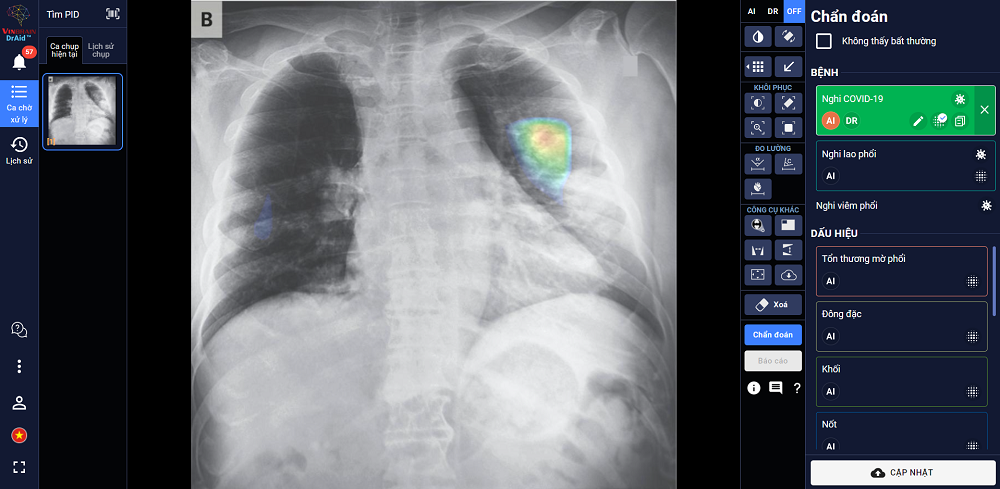

DrAid for Radiology (AI Trợ lý bác sĩ cho chẩn đoán hình ảnh y tế) là sản phẩm đầu tay của VinBrain và cũng là một trong những sản phẩm AI hoàn chỉnh đầu tiên của y tế Việt Nam. Ứng dụng được ra mắt phiên bản đầu tiên vào ngày 14/6/2020.

Sản phẩm có khả năng phát hiện, sàng lọc trên 21 dấu hiệu bất thường và bệnh lý về phổi, tim, xương trong vòng 5 giây với độ chính xác trên 89%; đồng thời có thể chia sẻ kết quả chẩn đoán thông qua QR code hoặc đường link. Đặc biệt, sản phẩm có khả năng tự cảnh báo Covid-19, kể cả các trường hợp không có triệu chứng hoặc tổn thương phổi nhẹ dựa trên X-quang ngực thẳng, kết hợp cùng xét nghiệm PCR giúp nâng cao độ chính xác, giảm thiểu tình trạng âm tính giả...

DrAid được ban giám khảo ACM SIGAI đánh giá cao vì ứng dụng những kỹ thuật tiên tiến trong lĩnh vực trí tuệ nhân tạo như phân loại nhiều lớp, suy luận theo cấu trúc cục bộ đến tổng quan, học chủ động, đào tạo đối nghịch, mạng nơ-ron tích chập phức hợp, nhận dạng giọng nói cho chỉnh sửa báo cáo y tế tự động, khoanh vùng tổn thương trên ảnh y tế...

Các kỹ thuật này được kết hợp với kiến thức máy học sử dụng công nghệ cao AI dựa trên mô hình với hàng trăm triệu tham số điểm ảnh (pixel) và dữ liệu lớn hàng triệu ảnh với mỗi ảnh có hàng triệu điểm ảnh (pixel), cùng nhiều kỹ thuật khác tạo nên một dịch vụ trí tuệ nhân tạo phục vụ y tế toàn diện.